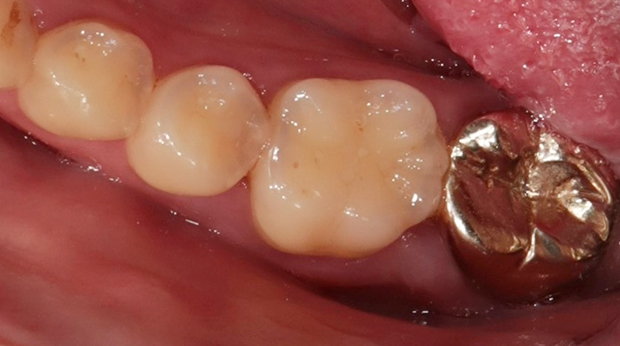

라미네이트